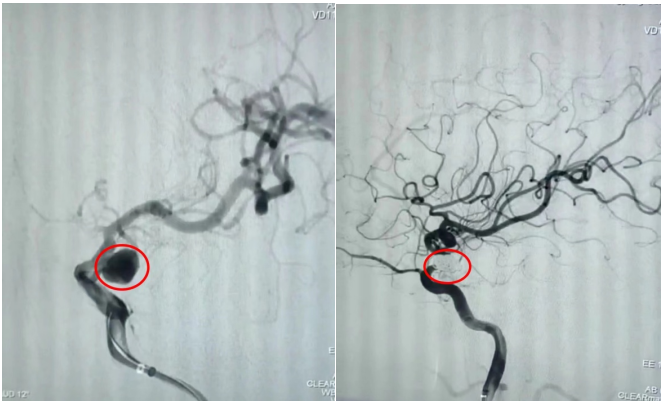

通訊員劉洋、劉立君報道: 9月2日家住衡山縣的劉爺爺從衡陽市中心醫(yī)院神經內科出院了。劉爺爺8月22日因左側頸內動脈后交通段動脈瘤破裂致蛛網膜下腔出血,病情危在旦夕,在衡山縣人民醫(yī)院行急診全腦血管造影明確病因后,連夜轉入衡陽市中心醫(yī)院神經內科治療。衡陽市中心醫(yī)院神經內科介入團隊立即接手病人,經過認真查看病人、細致分析病情,聯(lián)合介入室、麻醉科為病人緊急行動脈瘤介入栓塞術,手術順利,術后通過腦脊液置換、預防腦動脈痙攣、預防深靜脈血栓、預防感染等綜合治療措施,緩解了劉爺爺的頭痛癥狀,避免了并發(fā)癥的發(fā)生,10天后劉爺爺又回到了衡山縣人民醫(yī)院進行后續(xù)康復治療。